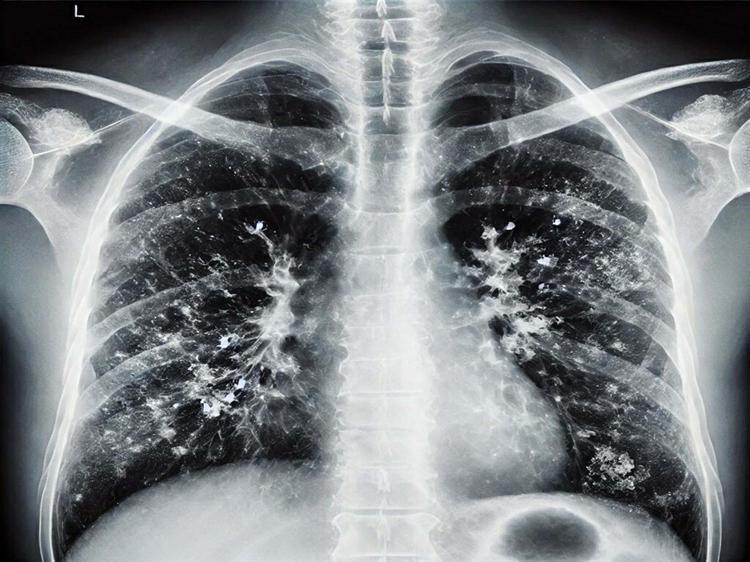

İzmir İl Sağlık Müdürlüğü Halk Sağlığı Hizmetleri Başkanlığı bünyesinde görev yapan Başkan Yardımcısı Doktor Metin Kızılelma, kış mevsiminin gelmesiyle birlikte solunum yolu enfeksiyonlarında görülen belirgin artışın aslında son derece doğal bir süreç olduğunu ifade etti. Ancak bu yaygın enfeksiyonlardan korunmak ve sağlığı muhafaza etmek için en temel çözüm yoluna dikkat çeken Kızılelma, hastalıklardan korunmanın en önemli etkeninin ise kesinlikle 'hijyen' şartı olduğunu vurguladı.

Solunum yolu enfeksiyonu etkenlerinin birden fazla olduğunu söyleyen doktor Kızılelma, "Bu etkene göre geçirdiğiniz solunum yolu enfeksiyonunun ağırlığı da değişebilir. O yüzden kişinin solunum yolu enfeksiyonu geçirirken bol sıvı alması ve dinlenmesi çok önemli. Ateş yüksekliği, öksürük olması, kendini kötü hissetmesi durumunda hasta mutlaka bir hekim tarafından muayene edilmeli" dedi.